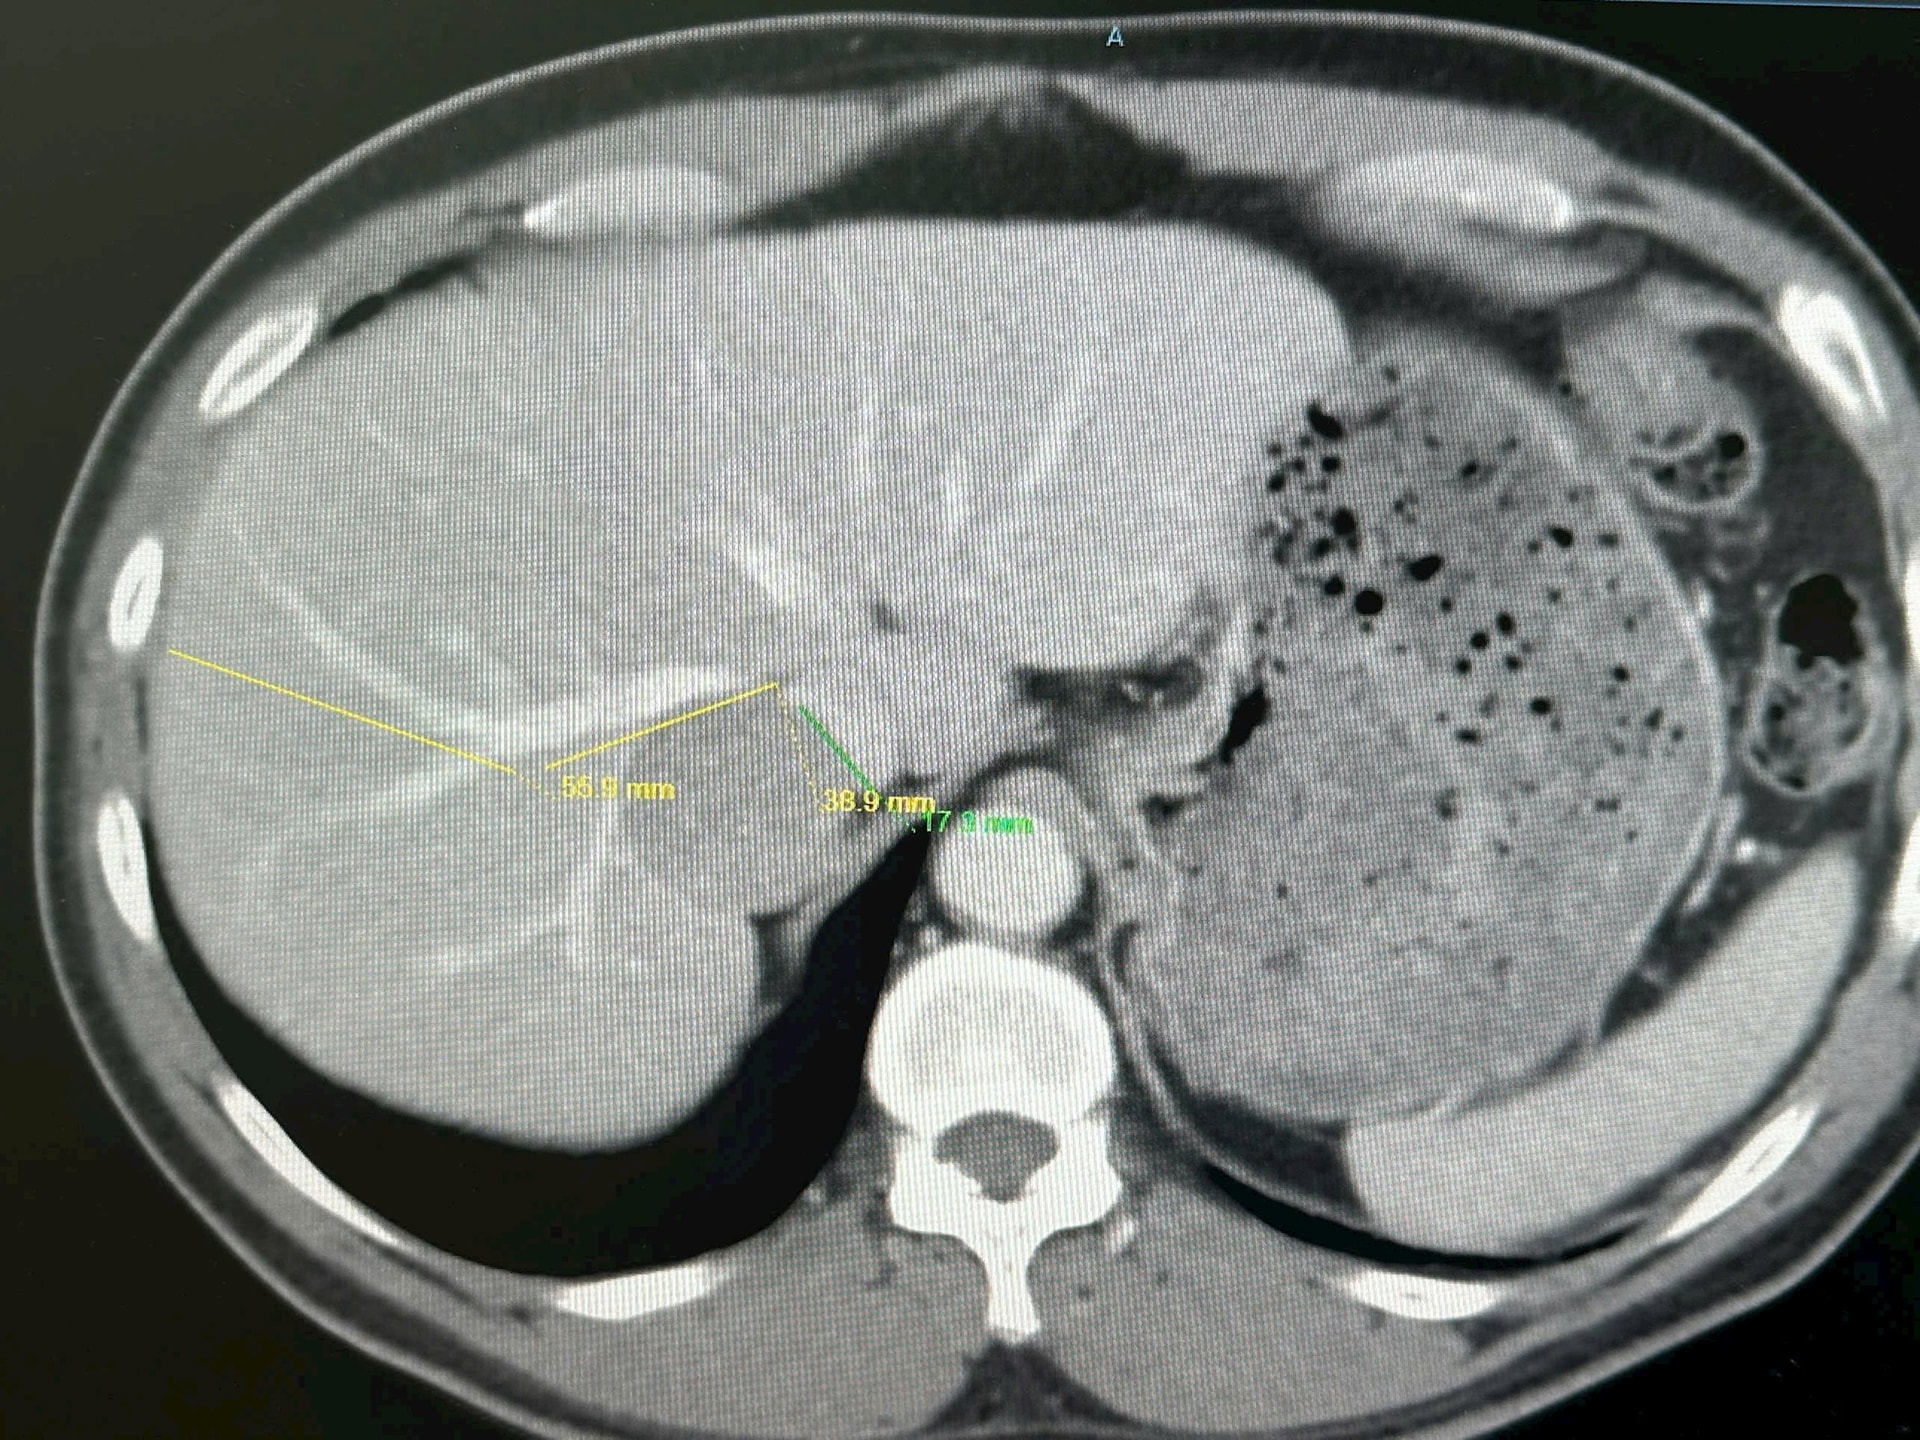

Sau đó, người bệnh đến Bệnh viện Quân y 175 để tiếp tục thăm khám và điều trị. Qua các xét nghiệm và chẩn đoán hình ảnh chuyên sâu, bác sĩ xác định khối u gan kích thước khoảng 4 cm nằm ở vị trí hiểm hóc, bị bao quanh và chèn ép nhiều mạch máu quan trọng của gan, đặc biệt là tĩnh mạch gan và tĩnh mạch chủ dưới.

Việc tiếp cận và cắt bỏ hoàn toàn khối u trở nên rất khó khăn, chỉ cần một sai sót nhỏ trong quá trình phẫu thuật cũng có thể gây rách mạch máu lớn, đe dọa trực tiếp tính mạng người bệnh.

Sau khi tiến hành hội chẩn đa chuyên khoa, các bác sĩ Bệnh viện Quân y 175 đã xây dựng phương án phẫu thuật chi tiết. Nhiều kỹ thuật chẩn đoán hình ảnh hiện đại được sử dụng nhằm đánh giá chính xác mối liên quan giữa khối u và hệ thống mạch máu, đồng thời chuẩn bị chiến lược kiểm soát mạch máu chặt chẽ để đảm bảo an toàn tối đa cho người bệnh.